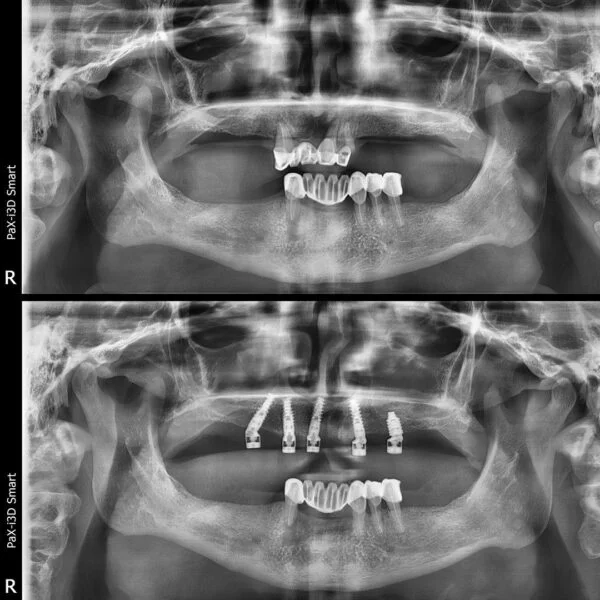

Implantul dentar este adesea recomandat deoarece prezintă foarte multe avantaje, iar, de multe ori, este unica soluție pentru protezarea unei edentații.